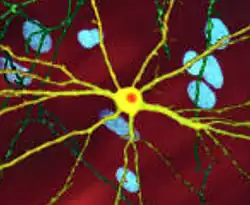

![]() | |

| An edited microscopic image of a medium spiny neuron (yellow) with an inclusion body (orange), which occurs as part of the disease process (image width 360 μm) | |

The toxic action of mHtt may manifest and produce the HD pathology through multiple cellular changes.[52][53] In its mutant (polyglutamine expanded) form, the protein is more prone to cleavage that creates shorter fragments containing the polyglutamine expansion.[52] These protein fragments have a propensity to undergo misfolding and aggregation, yielding fibrillar aggregates in which non-native polyglutamine β-strands from multiple proteins are bonded together by hydrogen bonds.[15] These aggregates share the same fundamental cross-beta amyloid architecture seen in other protein deposition diseases.[54] Over time, the aggregates accumulate to form inclusion bodies within cells, ultimately interfering with neuronal function.[15][52] Inclusion bodies have been found in both the cell nucleus and cytoplasm.[52] Inclusion bodies in cells of the brain are one of the earliest pathological changes, and some experiments have found that they can be toxic for the cell, but other experiments have shown that they may form as part of the body's defense mechanism and help protect cells.[52]